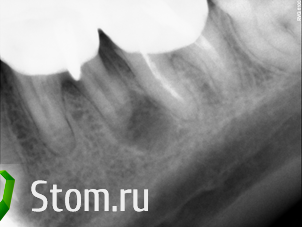

samsonov Опубликовано 16 января, 2012 Поделиться Опубликовано 16 января, 2012 были перелечены каналы,планировалась хирургия,пациент "потерялся" на год примерно, на повторных снимках - ... вы видите... Ссылка на комментарий

Elenushka Опубликовано 16 января, 2012 Автор Поделиться Опубликовано 16 января, 2012 зуб связан с кистой,на мой взгляд,только ощущение что похож на молочный моляр:-)....очень маленький. Ссылка на комментарий

samsonov Опубликовано 16 января, 2012 Поделиться Опубликовано 16 января, 2012 зуб связан с кистой,на мой взгляд,только ощущение что похож на молочный моляр:-)....очень маленький.+Из мезиобуккального текло содержимое кисты._- если это молочный,значит до меня неизвестный ортодонт переместил его назад...Маленький- не ислючается лизис апексов, но по ощущениям моиммезиальный не был разрушен... Ссылка на комментарий

DmitrySH Опубликовано 17 января, 2012 Поделиться Опубликовано 17 января, 2012 Ну, ладно.Мои 5 копеек.Верите,что у 4.6 обошлось без хирургического вмешательства?Слева- более поздний снимок. Слушайте, у вас такая "штука" на 4.6 которой вы решили заняться, а на 4.5 переодонтит оставляете без внимания. Как же так? Снимки до и после - разной контрастности. Я бы вообще на КТ сразу бы слал Ссылка на комментарий

samsonov Опубликовано 17 января, 2012 Поделиться Опубликовано 17 января, 2012 Слушайте, у вас такая "штука" на 4.6 которой вы решили заняться, а на 4.5 переодонтит оставляете без внимания. Как же так?Снимки до и после - разной контрастности. Я бы вообще на КТ сразу бы слал4.5. не пропущен.Это -выдержки из истории. Ссылка на комментарий